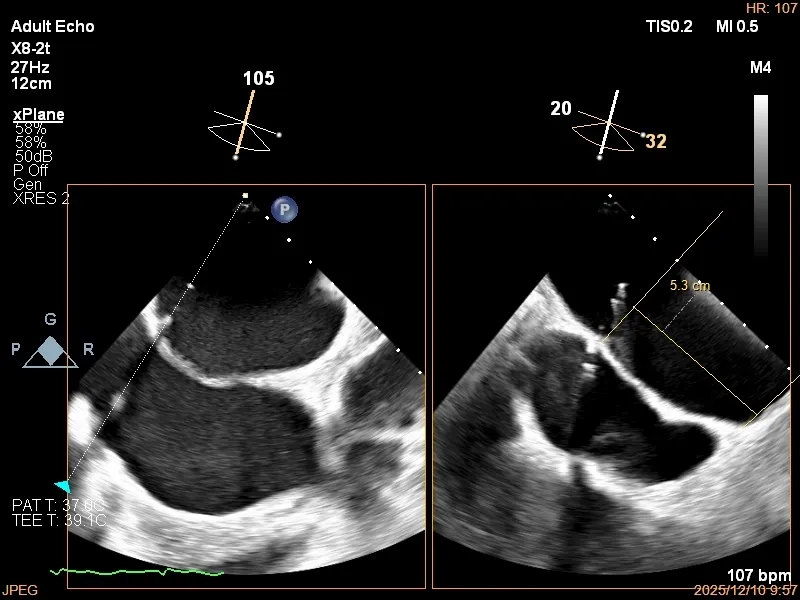

3D-TEE二尖瓣相关解剖学参数:后叶长度:22-25mm,前叶长度:31-34mm;瓣环AP径:47mm,ML径:48mm;瓣口面积:约7.8cm²;脱垂宽度:30mm,最大连枷间距:14mm。

术前即刻TEE进一步明确了二尖瓣反流的机制(DMR)及反流程度(5+),重点完善了病变区域二尖瓣解剖结构的评估,预估手术难点/影响手术效果的解剖结构为冗长的二尖瓣后叶(PML约25mm),宽大的脱垂(Flail Width约30mm),超大的连枷间距(Flail gap约14mm)。

全麻下穿刺右股静脉,在TEE指导下完成房间隔穿刺,穿刺处与二尖瓣环距离5.3cm。将Superstiff导丝送至左房,应用18F鞘管扩张穿刺部位,沿导丝将可操纵导引导管送入左房。

房间隔穿刺高度5.3cm